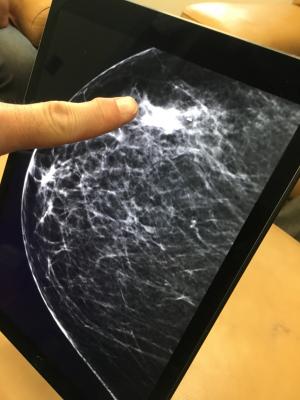

August 28, 2020 — Researchers at Karolinska Institutet and Karolinska University Hospital in Sweden have compared the ability of three different artificial intelligence (AI) algorithms to identify breast cancer based on previously taken mammograms. The best algorithm proved to be as accurate as the average radiologist. The results, published in JAMA Oncology, may lead the way in reorganising breast cancer screening for the future.

There are currently a large number of suppliers developing various AI-based medical imaging solutions. This study compares the ability of three of these to identify breast cancer in already taken mammograms.

The study included mammograms of 8,805 women between the ages of 40 and 74, all of whom had undergone breast cancer screening between 2008 and 2015. Of these, 739 had been diagnosed with breast cancer, either at the time of screening or within the following 12 months. The most successful of the three AI algorithms diagnosed the same percentage of women with cancer as the average radiologist.